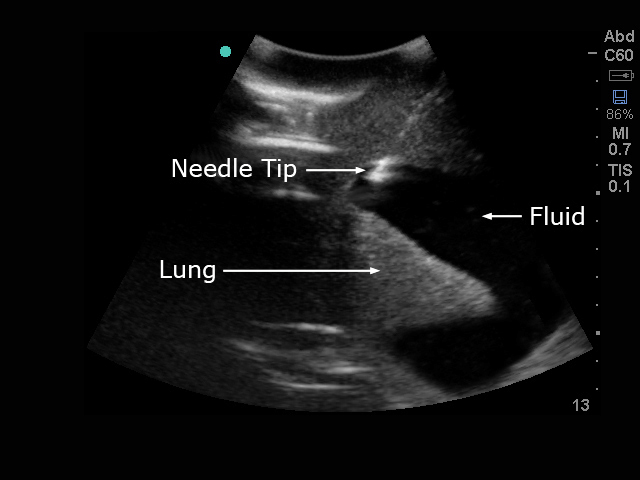

模型能够与任何超声影像检查设备连接使用,是练习提升经超声引导进行胸腔穿刺的理想模型。同时此模型还可用于练习非超声引导条件下胸腔穿刺,非超声引导胸廓造口术。